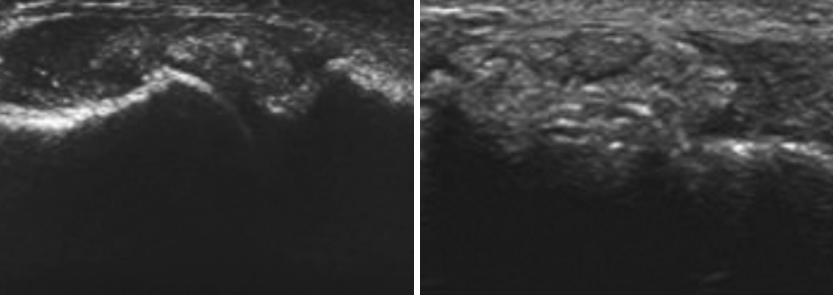

통풍은 통증과 부종(붓기)를 동반하는 일종의 관절염으로 정확한 명칭은 통풍관절염(Gout Arthritis)이라고 부릅니다. 혈액 내 요산 수치가 높아지면서 관절이나 생체 내 조직에 결정 형태로 쌓이게 되는데, 이런 요산염 결정이 염증 반응을 일으키면서 극심한 통증을 유발하는 질환입니다. 통풍이 생기는 원인으로는 신장에서 요산 배출이 원활하지 않거나 신장 기능은 정상인데 요산을 과도하게 만드는 식습관을 가지고 있어 생깁니다. 또한 비만인 사람에게 흔하게 나타날 수 있는 질병입니다.

요산은 퓨린(Purine)이라는 물질이 있는 음식을 생체 내에서 대사를 하고 남은 부산물입니다. 이 요산이 혈액내에서 농도가 높아지면 혈액, 체액, 관절액 내에 요산염 형태로 존재하게 되는데, 이런 요산염이 관절의 연골, 힘줄, 주위 조직 등에 쌓이면서 통풍이 발생합니다. 통풍은 보통 엄청난 통증과 붓기를 유발하게 되며, 심할 경우에는 관절의 변형과 불구를 유발하는 요인이 되기도 합니다. 관절의 변형과 불구 이외에도 신장질환, 신석증 등의 질환이 생기기도 하니 한 번 통풍을 겪은 환자들은 항상 조심해야 되는 질병입니다.

만성 통풍은 통풍의 증상이 관절염의 증상과 유사하게 나타나는 경우를 이야기합니다. 간헐적 통풍의 시기를 지나 요산염 결정이 침투한 관절 부위에 뻣뻣한 느낌과 통증을 계속 유발하게 됩니다. 또한 지속되면 피부에서 요산염이 나오기도 하고 요산염의 침투 부위의 변형이 일어나기도 합니다.